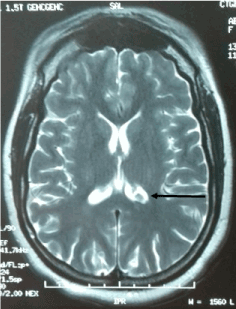

A 37 years old woman presented upper gastrointestinal bleeding. Upper endoscopy and biopsy confirmed a gastric MALT lymphoma (Figure 1). She also presented headache without localization signs at neurological examination. Cerebral MRI showed an expanding tissue tumor process of the left choroid plexus associated with peri-lesional edema (Figure 2). The biopsy could not be realized because high risk of bleeding due to the localization of the tumor.

Figure 2: Initial MRI showing an expanding tissue tumor process of the left choroid plexus associated with a signal anomaly opposite: peri-lesional edema (arrow).

Lymphoma was classified stage IV E according to modified Ann Arbor Classification. She received chemotherapy (CHOP protocol). Endoscopic control showed a regression of the lymphoma with histopathological remission according to GELA score. Headache improved after treatment and control MRI (Figure 3) showed partial regression of the tumor after systemic treatment (after 3 months).

Figure 3: Control Computed tomography showing partial regression of the cerebral lesion (arrow).